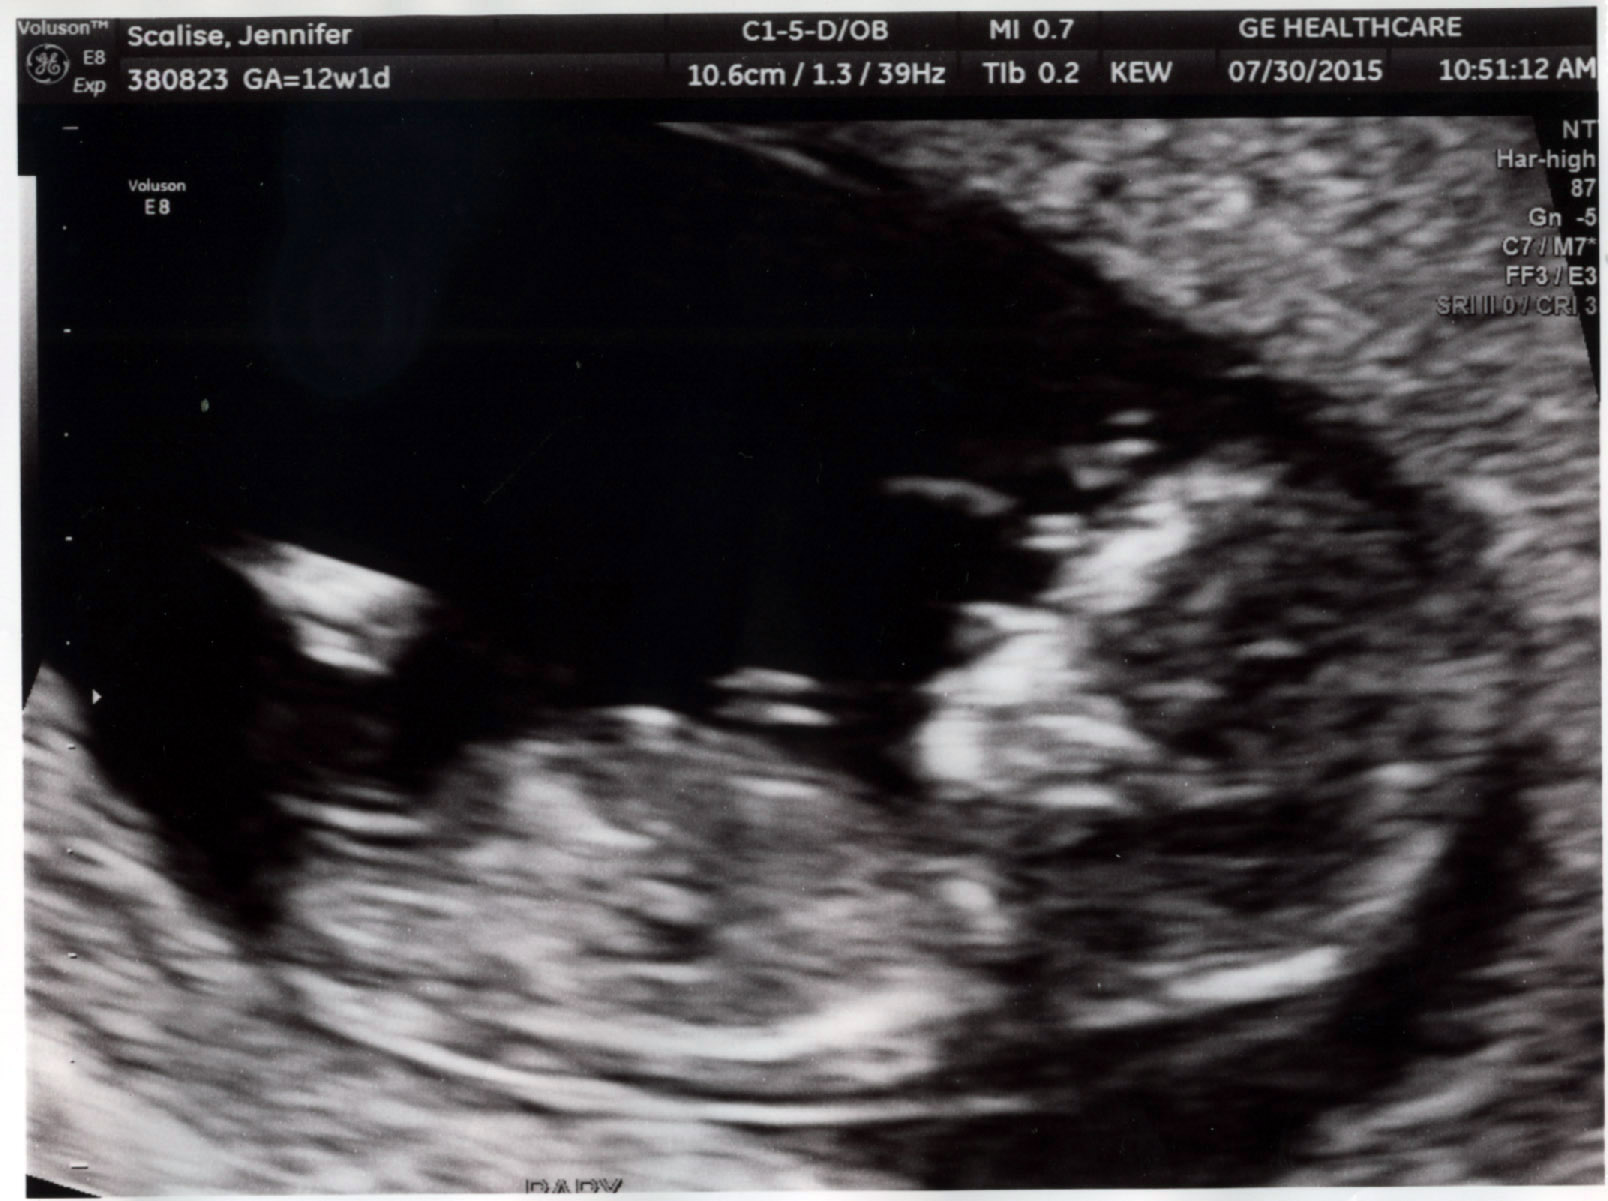

I just want to update that after 2 boys, this baby is a healthy baby GIRL!!!